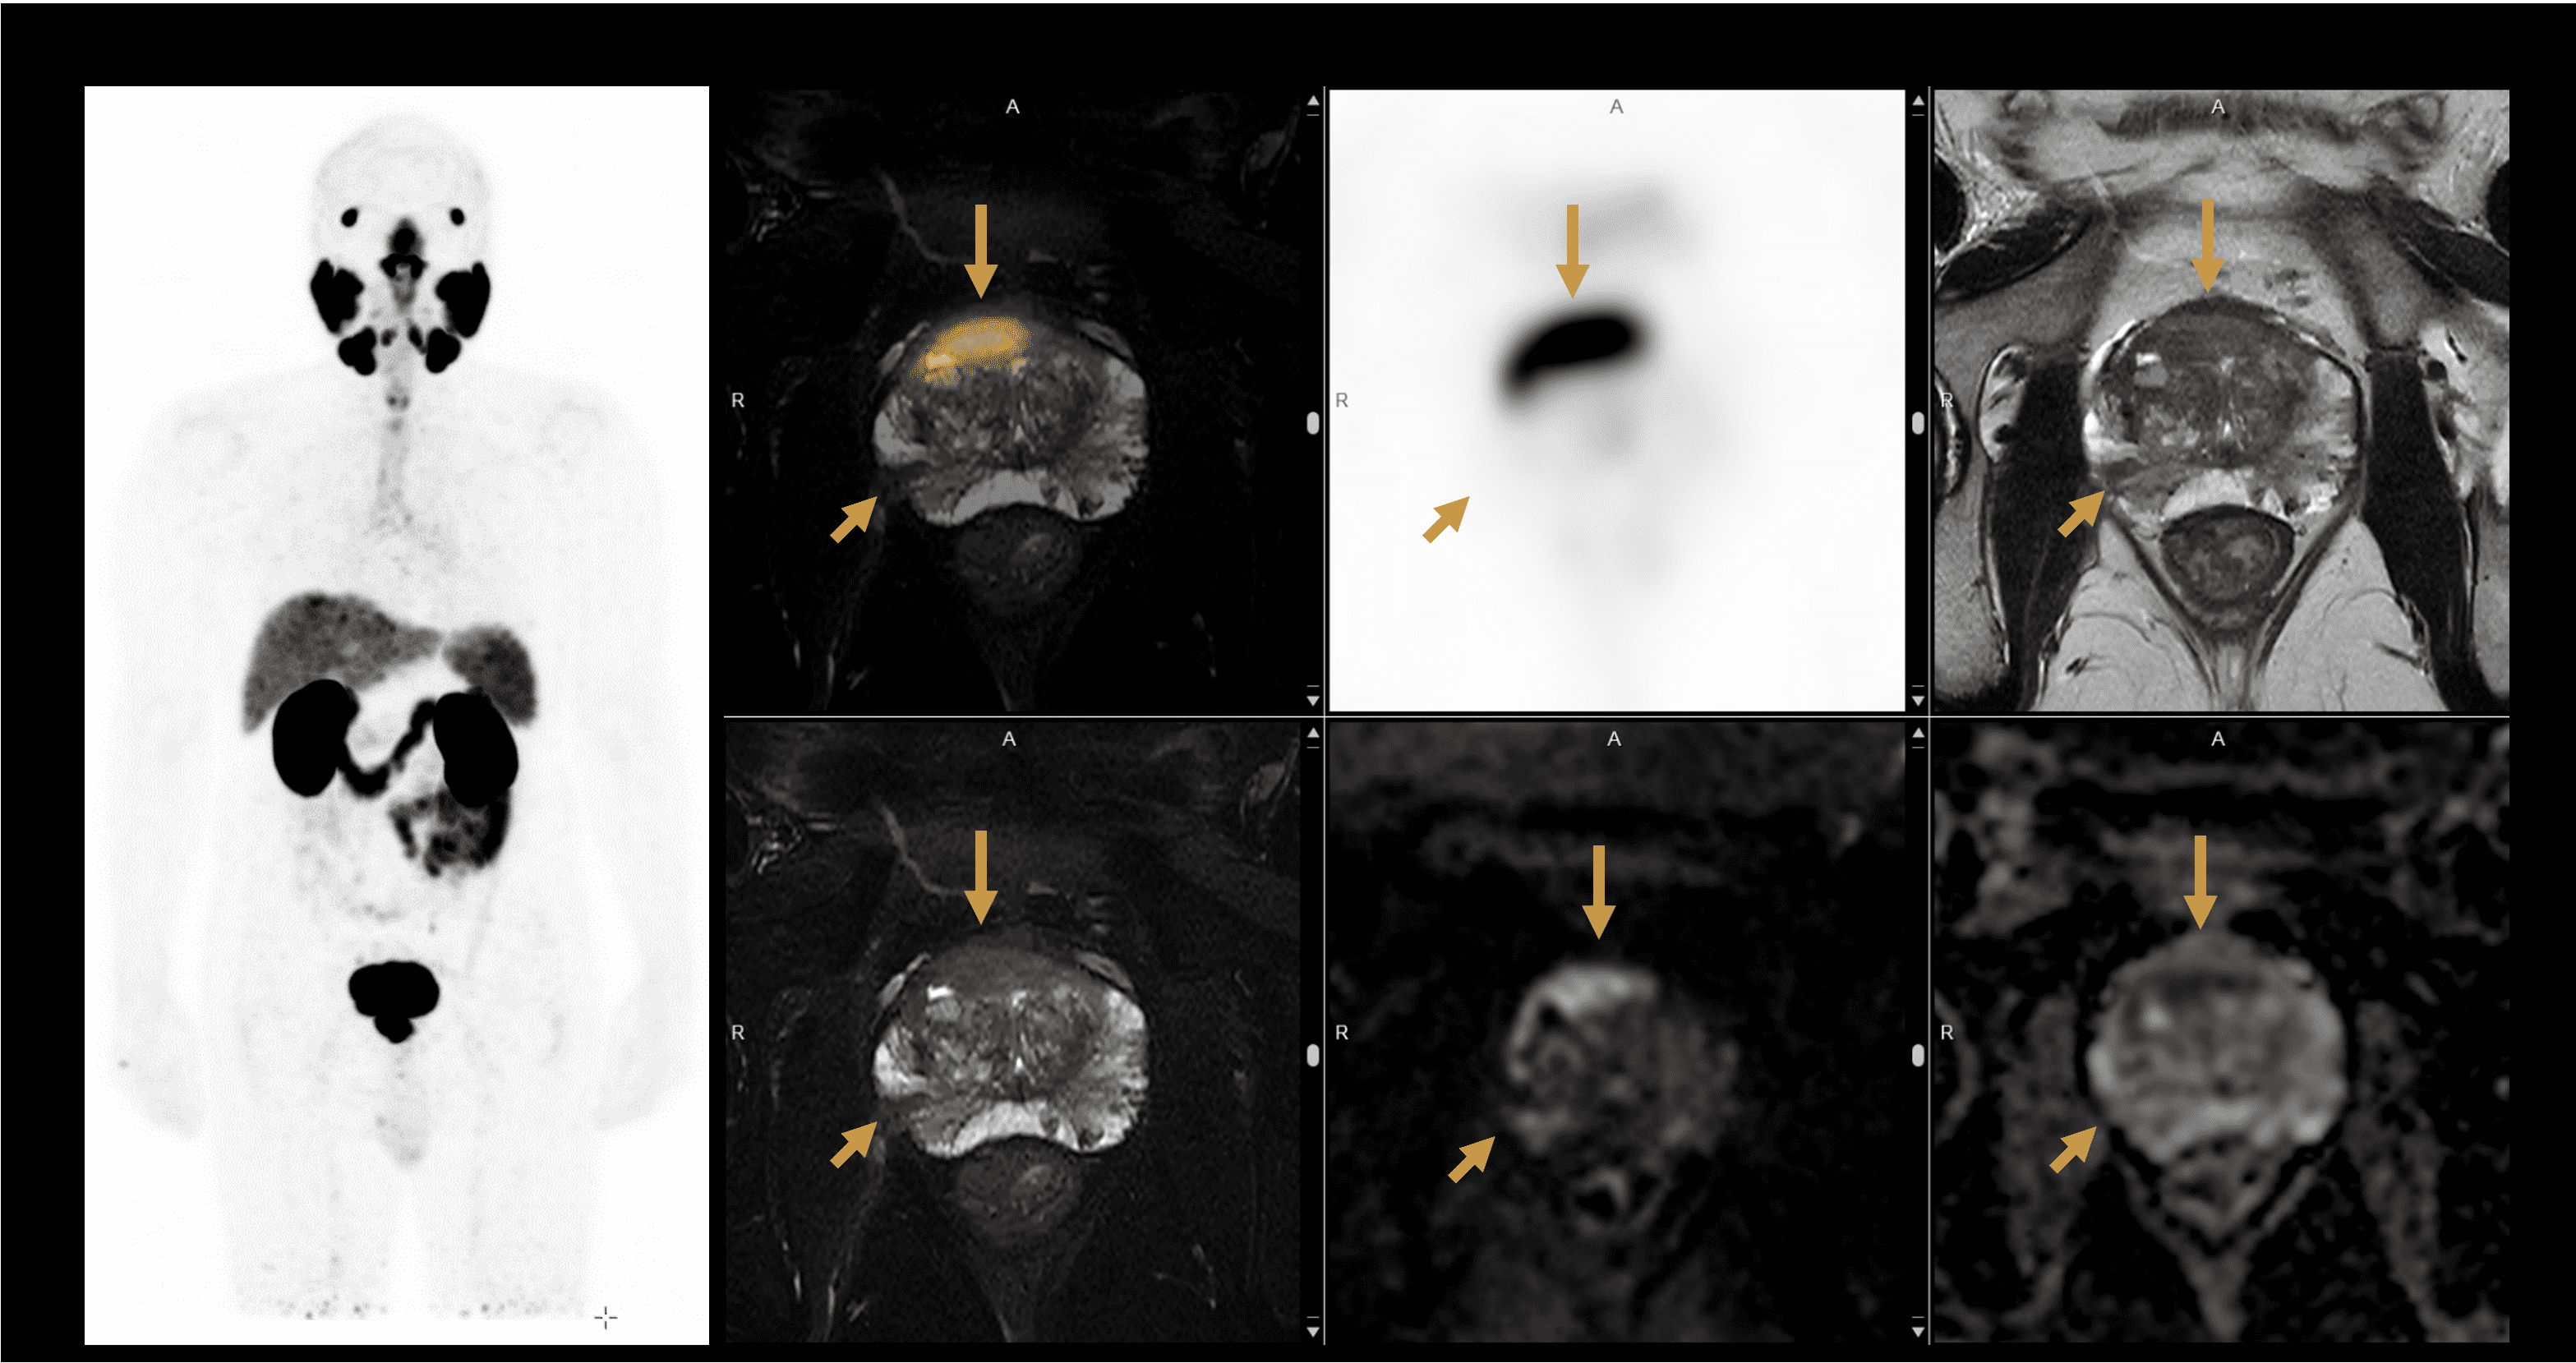

PET/MRI of the Prostate  with a Lesion

Assessment of prostate cancer with 68Ga-PSMA**

**Images Courtesy Of United Imaging